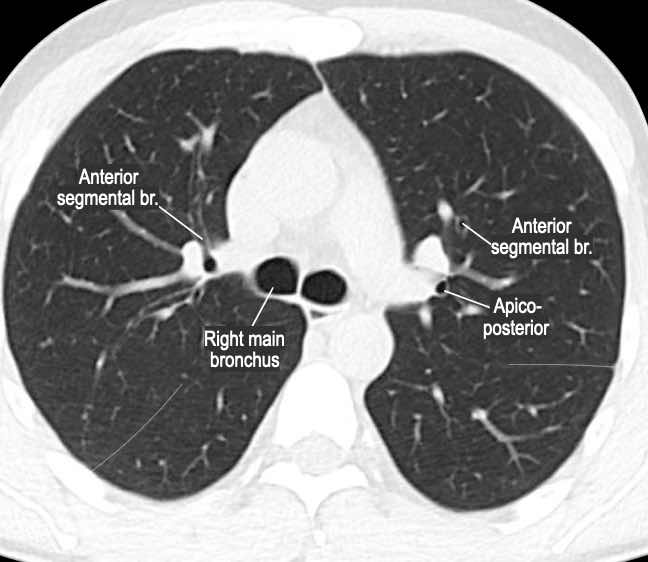

Phế quản trên CT

Cuộn qua các hình ảnh để quan sát khí quản phân chia thành phế quản chính phải và trái, sau đó tiếp tục phân chia thành các phế quản thùy và phế quản phân thùy.